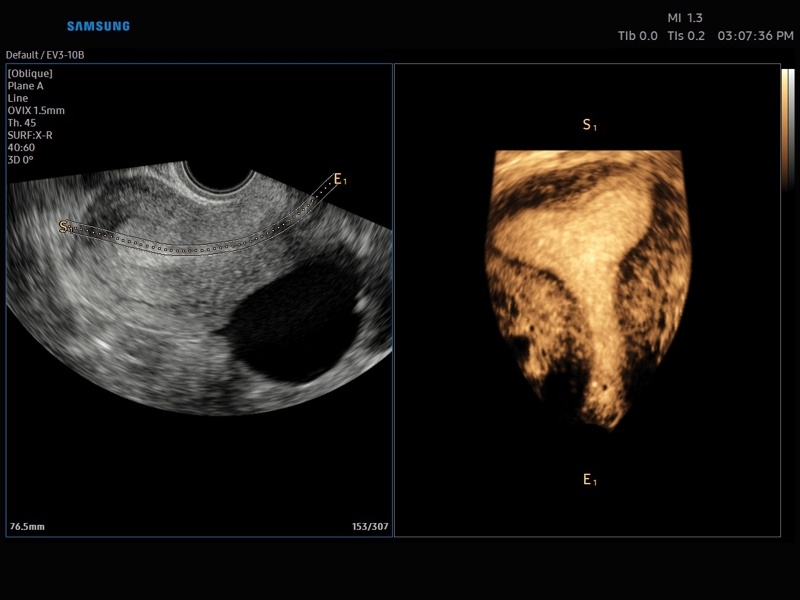

• OVIX(Oblique View eXtended) - получение фрагмента трехмерного изображения (в виде нескольких полупрозрачных сканов, последовательно наложенных один на другой) в направлении произвольного косого среза трехмерного объекта исследования.

• 3D - трехмерное сканирование объемными датчиками в статическом режиме в серой шкале и восстановление объемной структуры сосудов в режиме цветного / энергетического допплера (необходим Static 3D).

• 4D - трехмерное сканирование объемными датчиками в реальном масштабе времени (необходима опция Smart 4D).